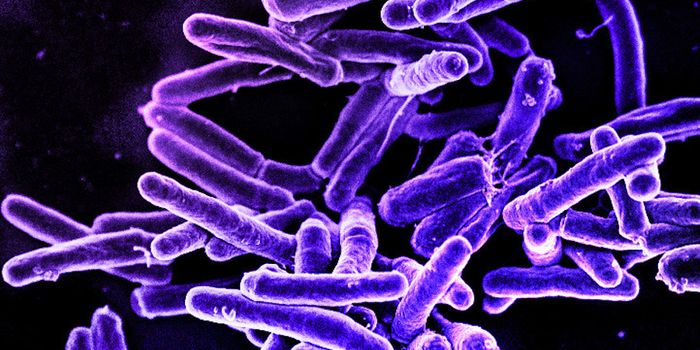

NOV 10, 2022MicrobiologyMycobacterium tuberculosis is the pathogenic bacterium that causes TB, which is still a major public health problem in m ...